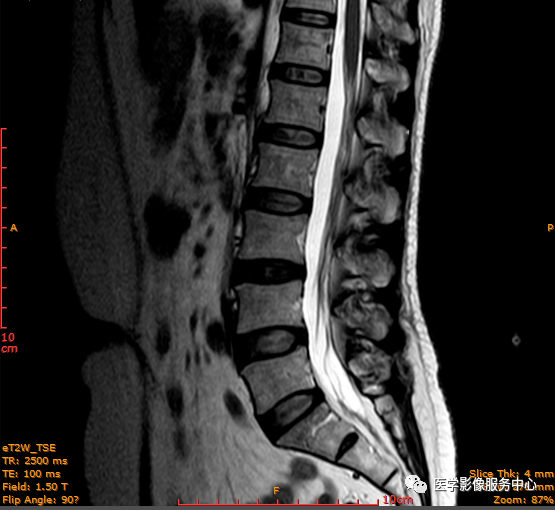

T1矢状位

日常工作因腰腿疼痛来检查腰椎MRI的很多,而腰腿疼痛并不一定就是腰椎椎间盘突出或膨出导致的,我们应该需要知道椎间盘HIZ也会引起腰腿疼痛,这种椎间盘源性的疼痛我们不能“忽略”;椎间盘后方HIZ并不少见,椎间盘后方 HIZ 在 T2WI 的局限性高信号、T1WI 呈局限性较低或等信号意味着通常所指的纤维环破裂伴随肉芽组织长入;而 T1WI、T2WI 均呈高信号可能是钙化组织。